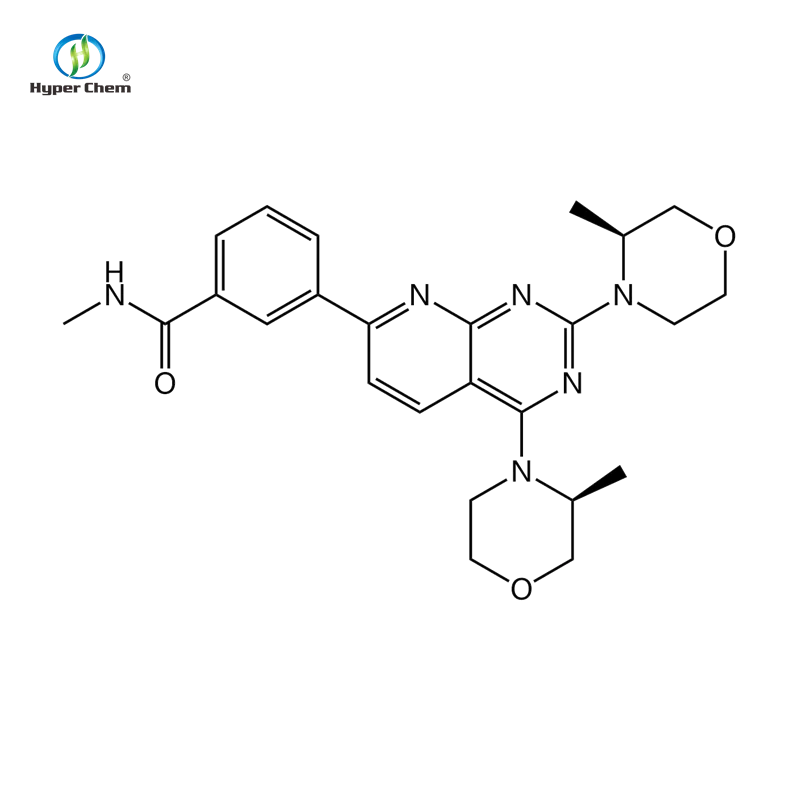

Quick Details Port: Any port in China Supply Ability: 10000 Kilogram/Kilograms per Month Other Names: ETHYL 5-AMINO-1-METHYLPYRAZOLE-4-CARBOXYLATE Type: pharmaceutical intermediates,Syntheses Material Intermediates Test Method: HPLC Test EINECS No.: 626-277-3 Purity: 98% Other Country: guangdong MF: C7H11N3O2 Appearance: Yellow Application: API CAS No.: 31037-02-2 Packaging Detail: Packing:1kg/bad,25kgs/drum Two plasti-bags inside and Paper-drums or as customer’s requirements Product Description Description & Specification Category Pharmaceutical Raw Materials, Fine Chemicals, Bulk drug Standard Medical standard Shelf life 2 years Storage should be stored in a well-closed container at low temperature, keep away from moisture, heat and light. Test Item Standard: USP Identification IR spectrum similar to that of RS HPLC retention time similar to that of RS Related substance Total impurities: NMT0.3% Single impurity: NMT0.1% Heavy metals NMT 10ppm Loss on drying NMT0.5% Residue on ignition NMT0.1% Assay 98.5%-101.0% Product Photo Packaging & Shipping Why Choose Us 1.Selecting raw materials strictly,our products are the highest purity.2.Reasonable and competitive price. Provide the best and professional service.3.Fast delivery of the samples ,samples from stock. Reliable shipping way.4.Full experience of large numbers containers loading in Chinese sea port.5.Best after-service after shipment .6.Professional documents for your custom clearance. FAQ Q: How to start orders or make payments?A: […]